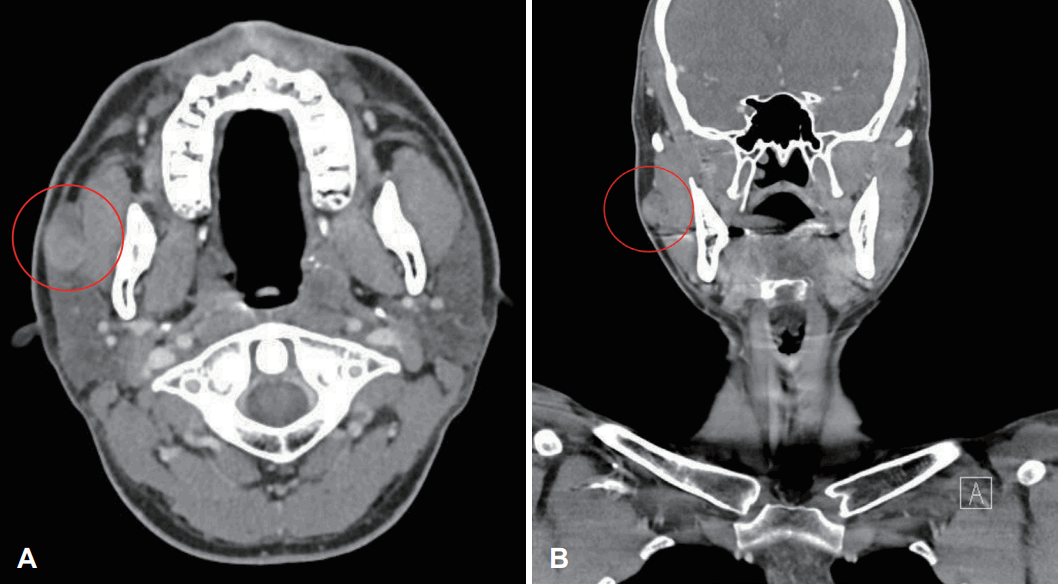

24세 남자 환자가 내원 2년 전 처음 발견하고 내원 6개월 전부터 커지는 우측 뺨의 종괴로 내원하였다. 자가면역질환을 포함한 침샘 부위 염증 등의 과거력 및 수술력은 없었다. 환자는 종괴로 인한 통증 등의 증상은 호소하지 않았다. 신체 검사에서 우측 뺨에 약 1.5×2 cm 크기의 단단하고 유동성이 있는 종괴가 촉진되었고 압통 및 안면신경 마비 증상은 없었다. 초음파 유도 세침흡인검사에서 다형선종 의증이 진단되었다. 경부 컴퓨터단층촬영(CT)에서 우측 이하선 전방에 22 mm의 뷸균질하게 조영 증강되는 종괴가 확인되어 영상의학적으로 우측 이하선 전방의 다형선종이 의심되었다(Fig. 1). 종괴는 2 cm 크기에 충분한 유동성을 가졌으며, 1/2 정도가 입안에서 만져졌으며 피부쪽에서 종괴의 2/3 이상이 촉진되었다. 구강 내에서 종괴의 촉진 정도가 구강 내 접근법의 가능성을 결정하는 중요한 요소이기에 위와 같은 이학적인 검사를 통해 구강 내 접근법을 통한 수술이 가능할 것으로 판단하였으며 젊은 환자에서 미용적인 장점을 고려하여 전신마취하에 구강 내 접근법을 통한 부이하선 종괴 절제술을 계획하였다. 수술 전 환자와 보호자에게 구강 내 접근법을 먼저 시도하고 만약 실패하면 외부 접근을 통한 절제술도 시행할 수 있다는 설명을 하였다.

Radiologic Neck CT finding. Red circle indicating enhancing mass lesion in the right anterior parotid gland on axial (A) and coronal view (B).